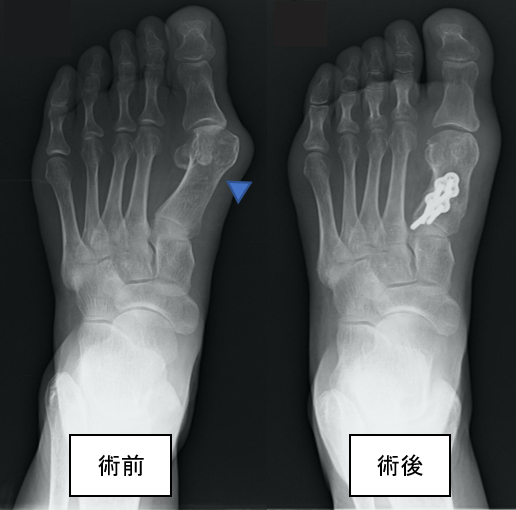

図2.外反母趾の骨切り術前後のX線画像。

術前では、第一中足骨と呼ばれる骨が大きく内側に向いており、母趾が外反しています(▲)。

術後は、骨切りによって変形が強制されています。